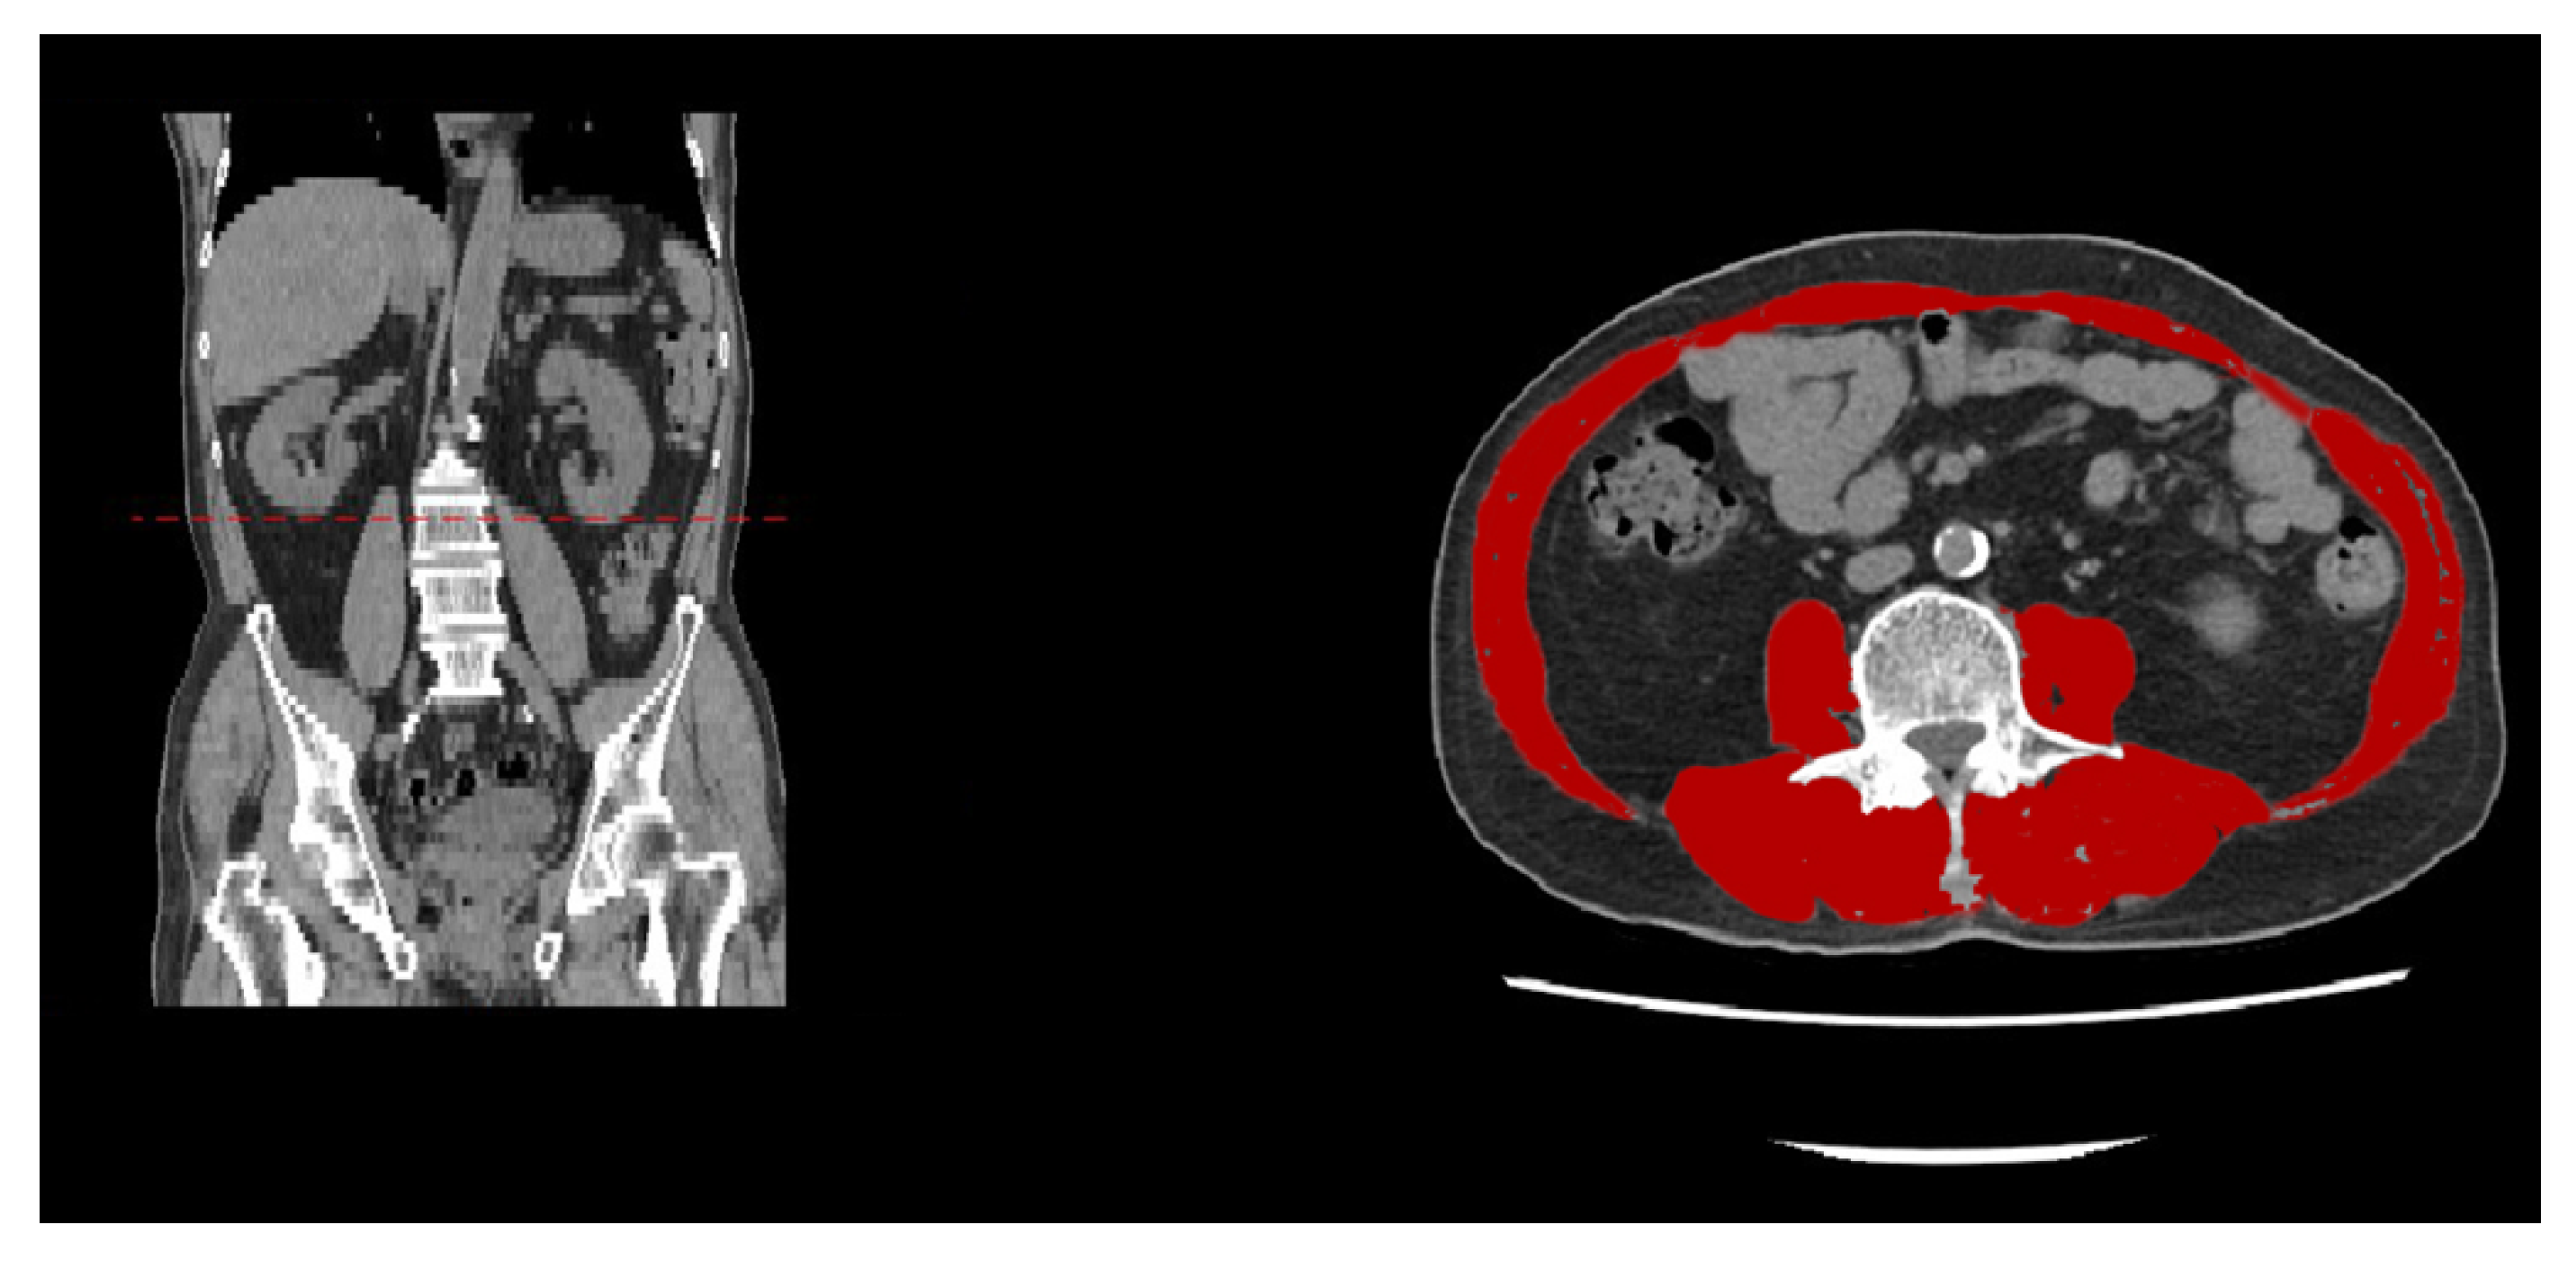

- Derstine, B.A.; Holcombe, S.A.; Ross, B.E.; Wang, N.C.; Su, G.L.; Wang, S.C. Skeletal muscle cutoff values for sarcopenia diagnosis using T10 to L5 measurements in a healthy US population. Sci. Rep. 2018, 8, 11369. [Google Scholar] [CrossRef]

- Lee, K.; Shin, Y.; Huh, J.; Sung, Y.S.; Lee, I.S.; Yoon, K.H.; Kim, K.W. Recent Issues on Body Composition Imaging for Sarcopenia Evaluation. Korean J. Radiol. 2019, 20, 205–217. [Google Scholar] [CrossRef]